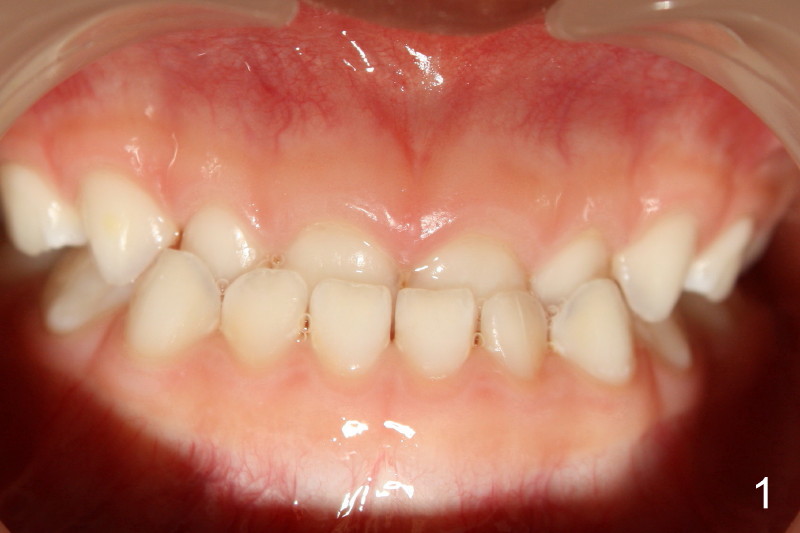

Clinical exam shows normal general development. The palate is not narrow. The prominent feature is anterior cross bite with lower midline shifting to the right approximately 1 mm (Fig.1). Profile appears within normal limit (Fig.2).